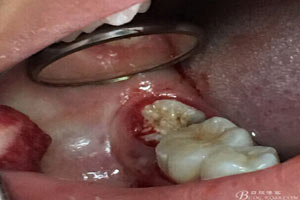

圖3.取出棉球口內(nèi)發(fā)現(xiàn)37合面有開(kāi)髓孔,探針出血,頰側(cè)牙齦紅腫

圖7.37牙冠碎裂。多生牙壓迫吸收程度嚴(yán)重。

圖9.清理牙槽窩過(guò)后。多生牙的牙冠暴露在牙槽窩內(nèi)。